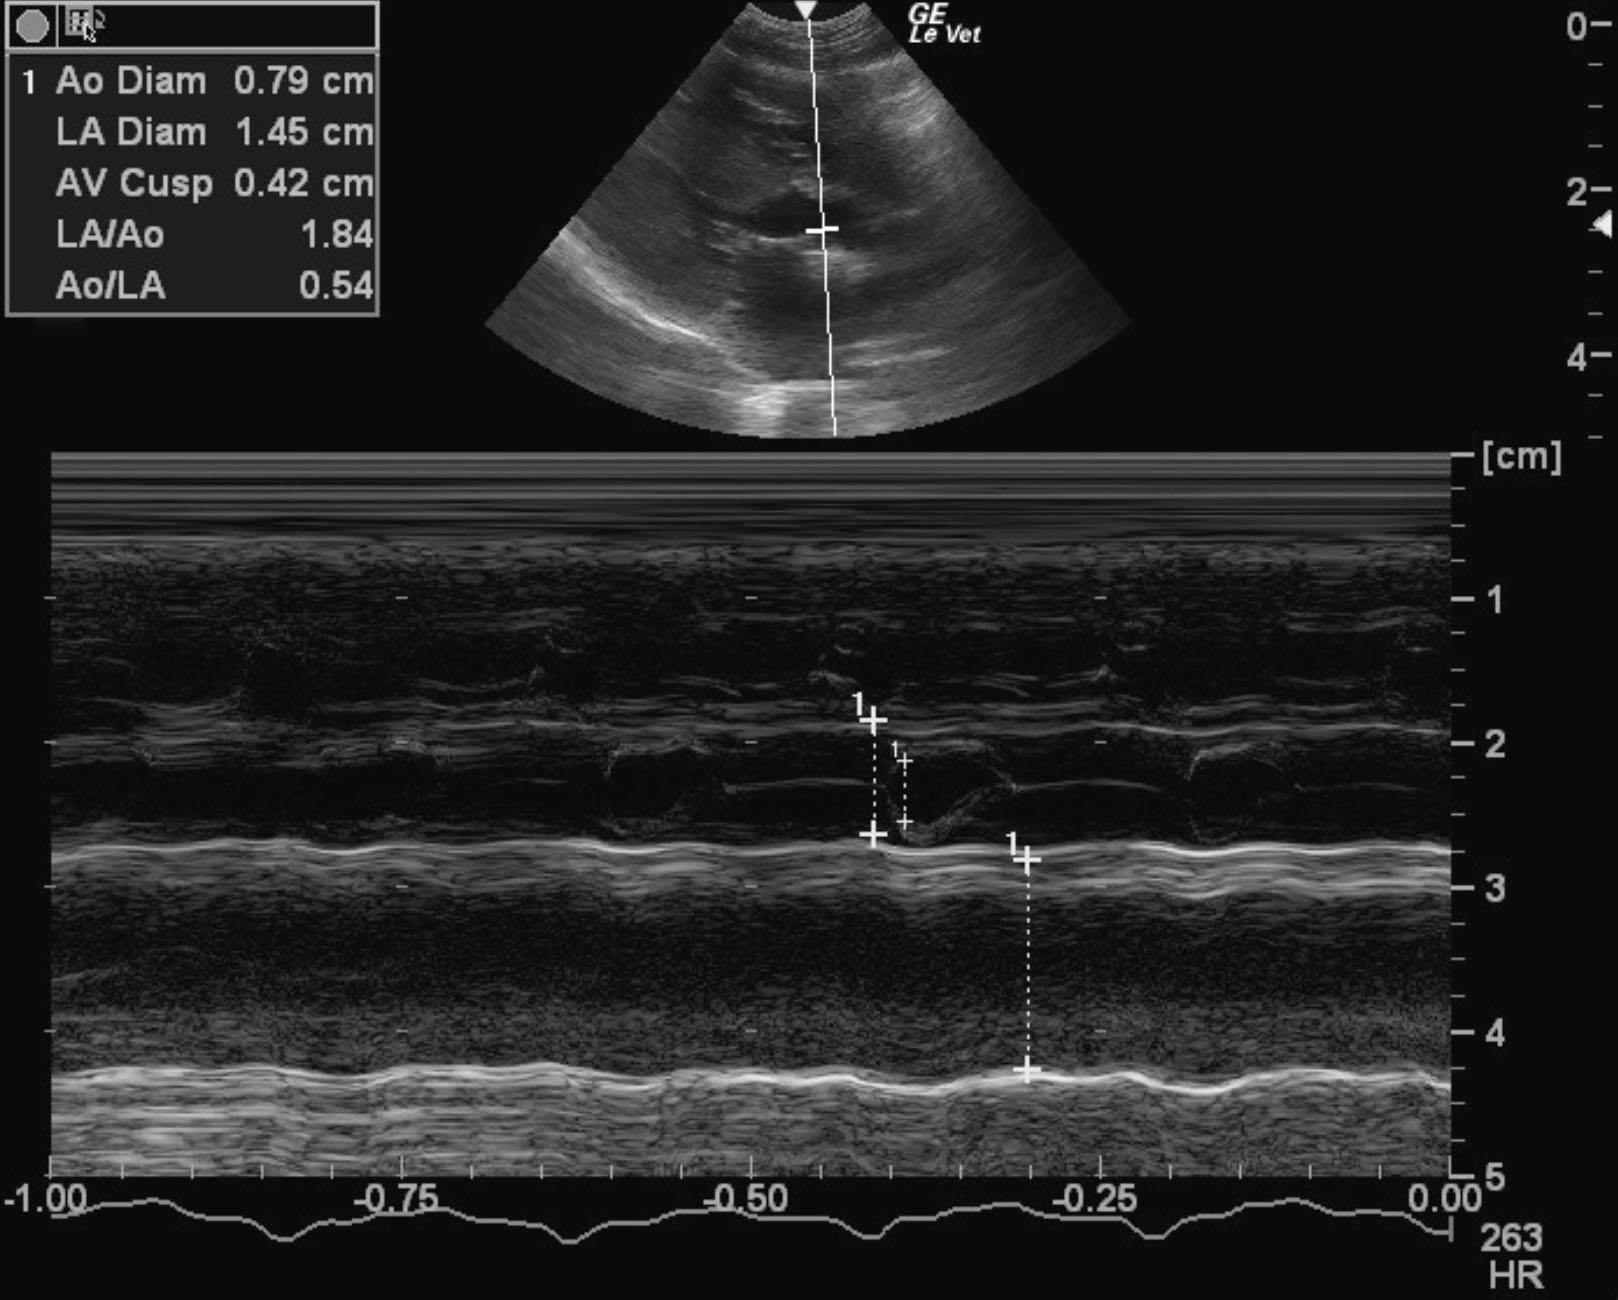

A 1-year-old MN DSHcat with a history of cardiac disease that was being treated with Plavix, enalapril, pimobendan, furosemide, and atenolol was presented for evaluation of weakness and dyspnea.

Physical exam: tachycardia (200-400bpm) and a grade III/VI heart murmur